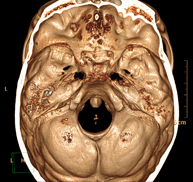

- Neuroradiology

- Skull CT

Radiological test that provides high definition anatomical images of the skull (brain stem, cerebellum, cerebrum, cranial calotte, etc.) using CT (Computed Tomography) equipment. Indicated for: trauma, headache, memory disorders, sudden loss of strength in a limb or half of the body.